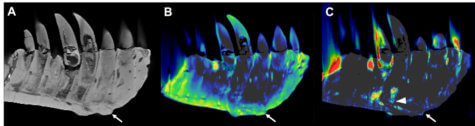

The German team used a non-invasive technique called DECT (dual-energy computed tomography) to make this discovery. The scans detected a significant accumulation of the element fluorine, a finding linked to brittle bones.

Dr. Hamm adds the mass and fluorine buildup supports the diagnosis of tumefactive osteomyelitis, an infection of the bone.

The imaging method has important implications in paleontology as an alternative to assessment methods that damage fossil samples. Dr. Hamm explained DECT deploys X-rays at two different energy levels to provide information about tissue composition and disease processes.

“We hypothesized that DECT could potentially allow for quantitative noninvasive element-based material decomposition and thereby help paleontologists in characterizing unique fossils,” Dr. Hamm says in a media release.

“We needed to adjust the CT scanner’s tube current and voltage in order to minimize artifacts and improve image quality,” Dr. Hamm adds. “While this is a proof-of-concept study, noninvasive DECT imaging that provides structural and molecular information on unique fossil objects has the potential to address an unmet need in paleontology, avoiding defragmentation or destruction.”